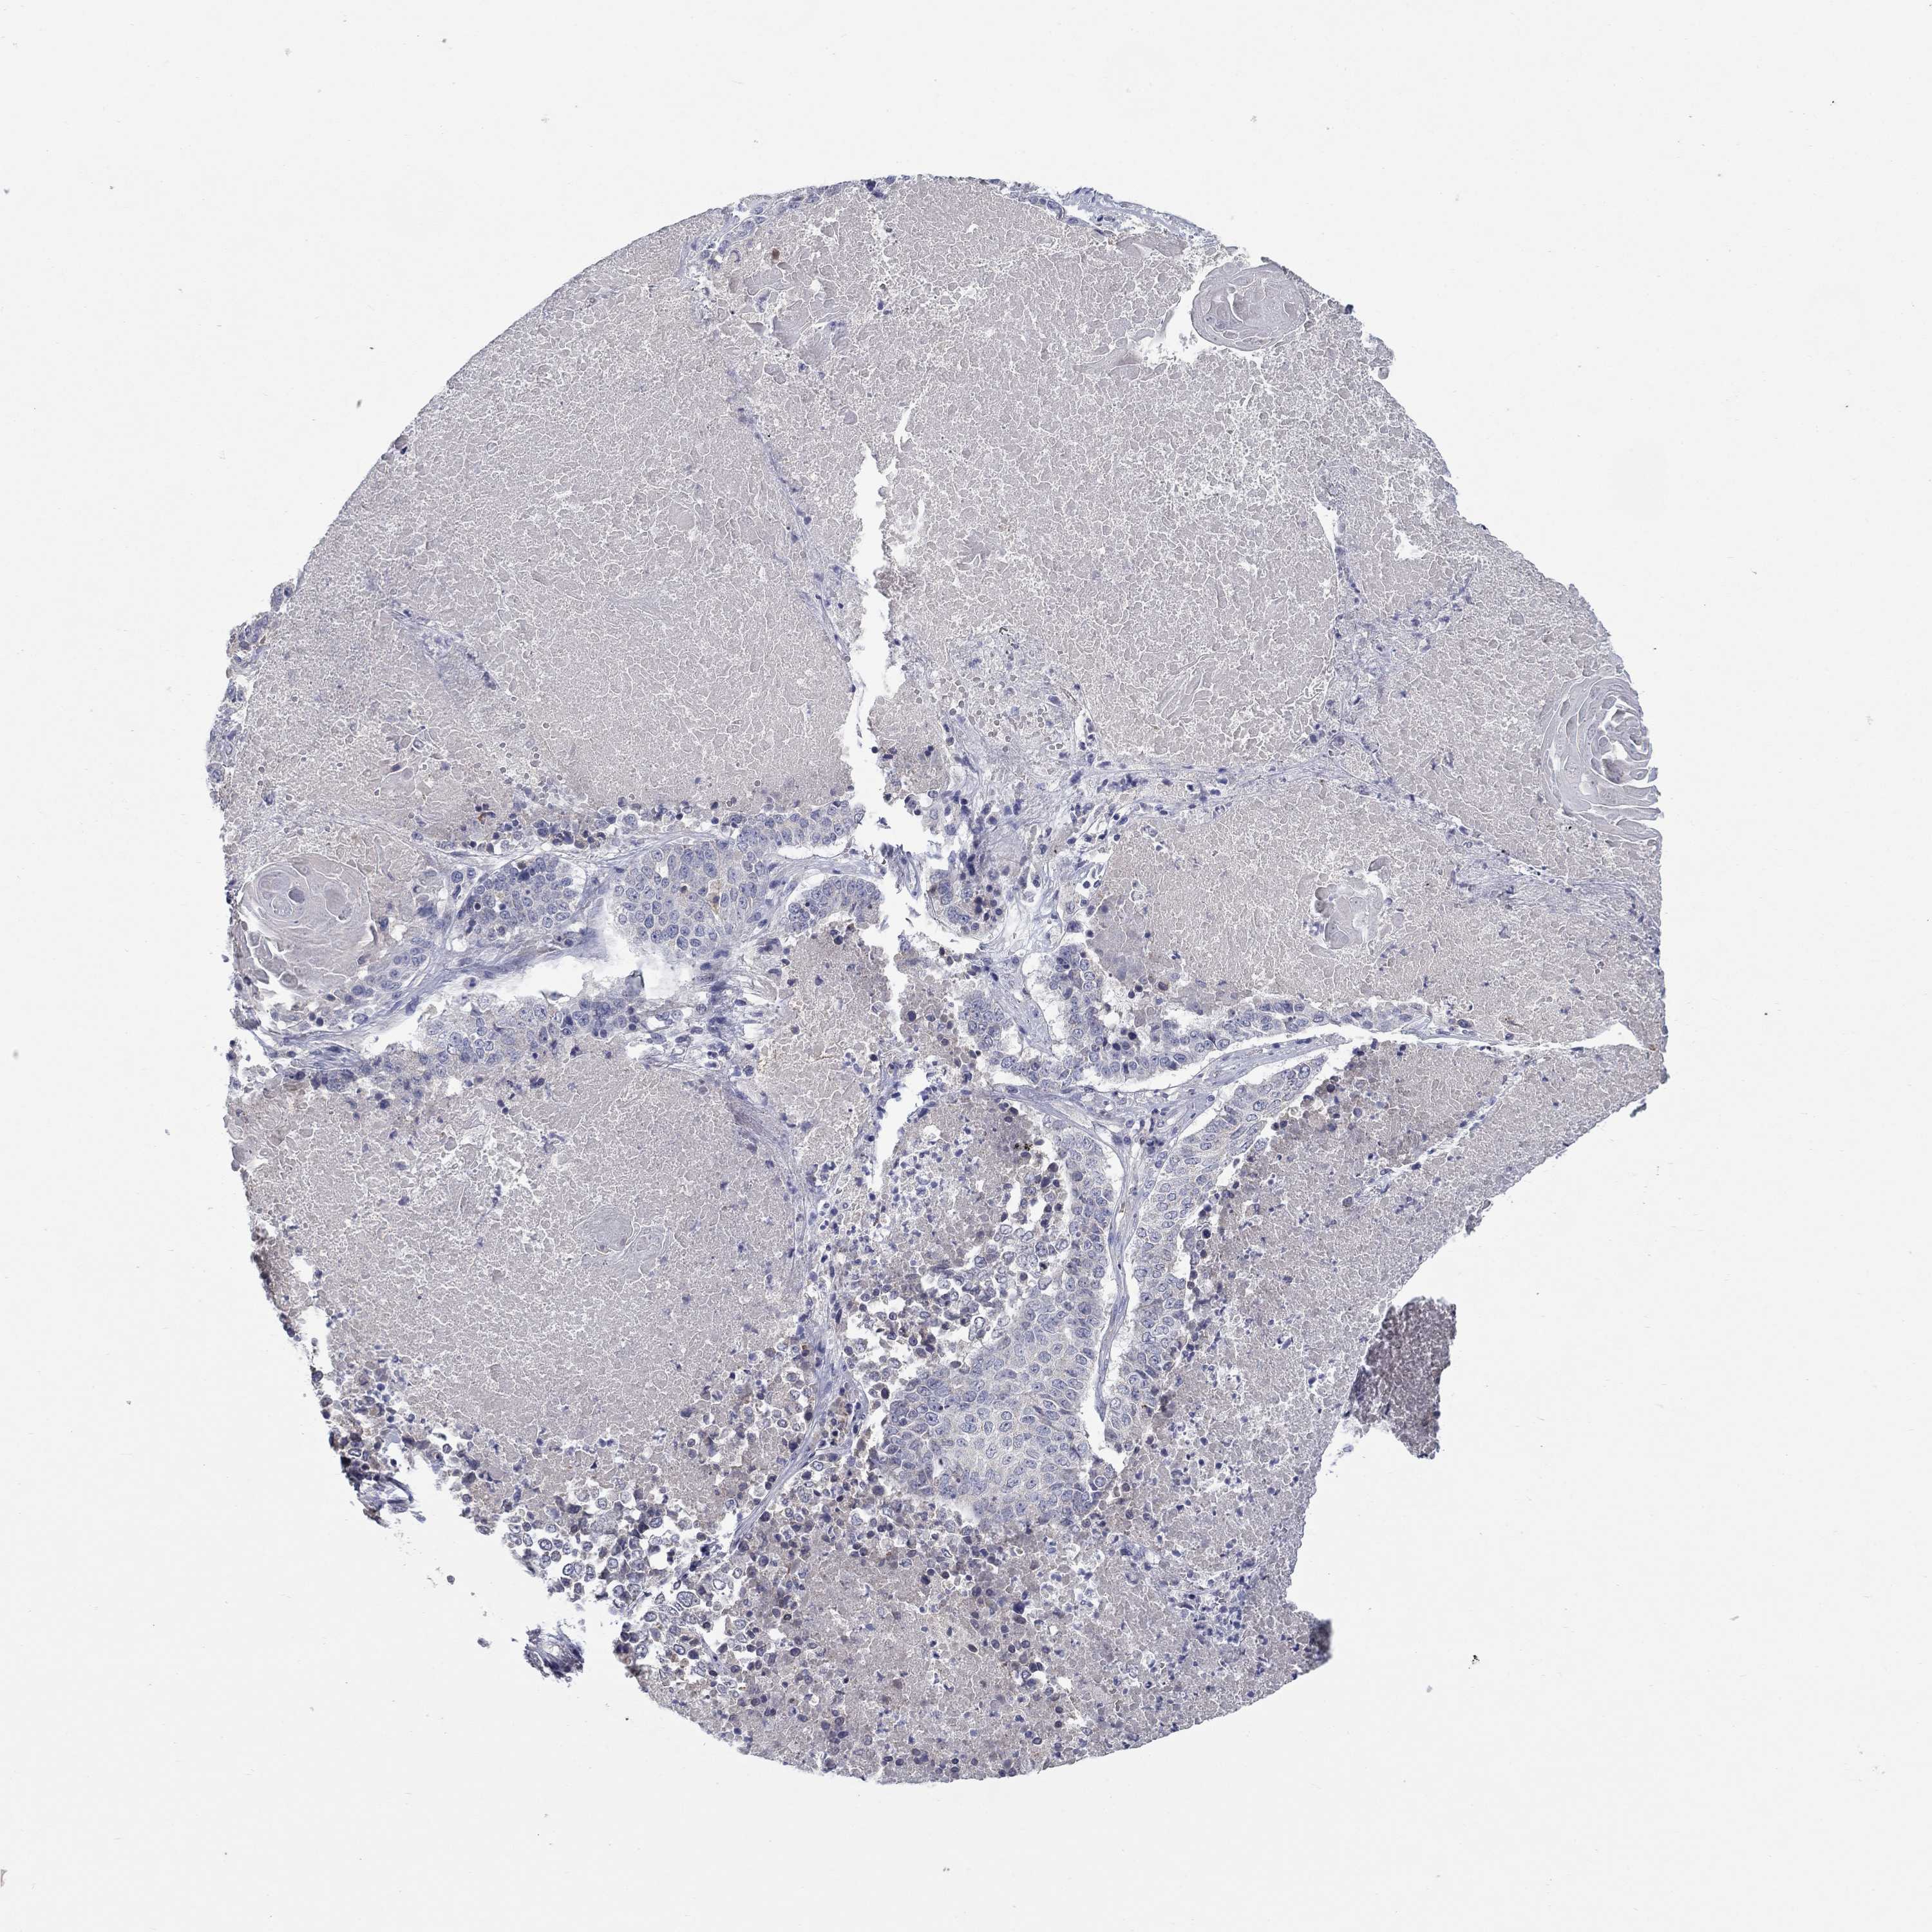

CANCER LUNG CANCER Show tissue menu

LUAD TCGA LUAD VALIDATION LUSC TCGA LUSC VALIDATION PROTEIN LUAD CPTAC PROTEIN LUSC CPTAC PROTEIN EXPRESSION

ANTIBODIES

AND

VALIDATION